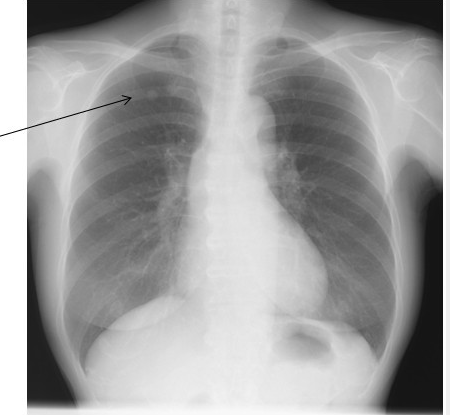

結節影のレントゲンChest radiography showing a nodular shadow in the upper | Open-i

結節影や腫瘤影は管を超えて、あるいは破壊してより大きくなっている病変を示唆する(→悪性の可能性も考える)。

【結節影、腫瘤影について】